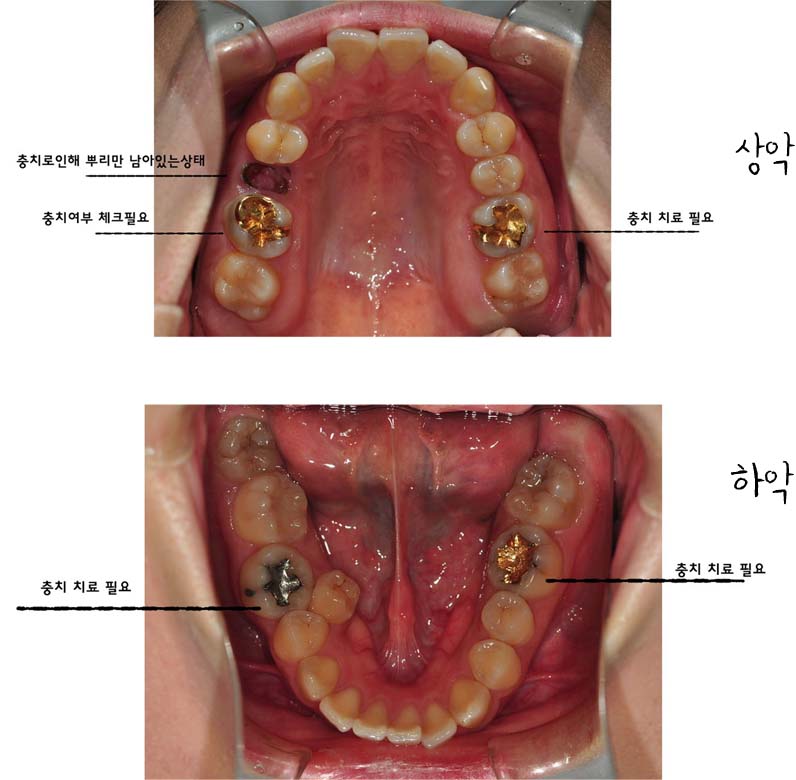

일단은 교정전 단계가 충치치료(충치 없으면 생략)- 발치- 치아 본뜨기- 킬본 교정기 제작 이런단계로 넘어가는데

저는 충치가 있어서 일단 어금니 위 아래 두개씩 치료를 받아야 한다고 했어요 그리고제가 안쪽 어금니에 잇몸이 많아 교정기 부착이 잘안될수 있어 잇몸을 살짝 잘라야 한다고 하더라구요